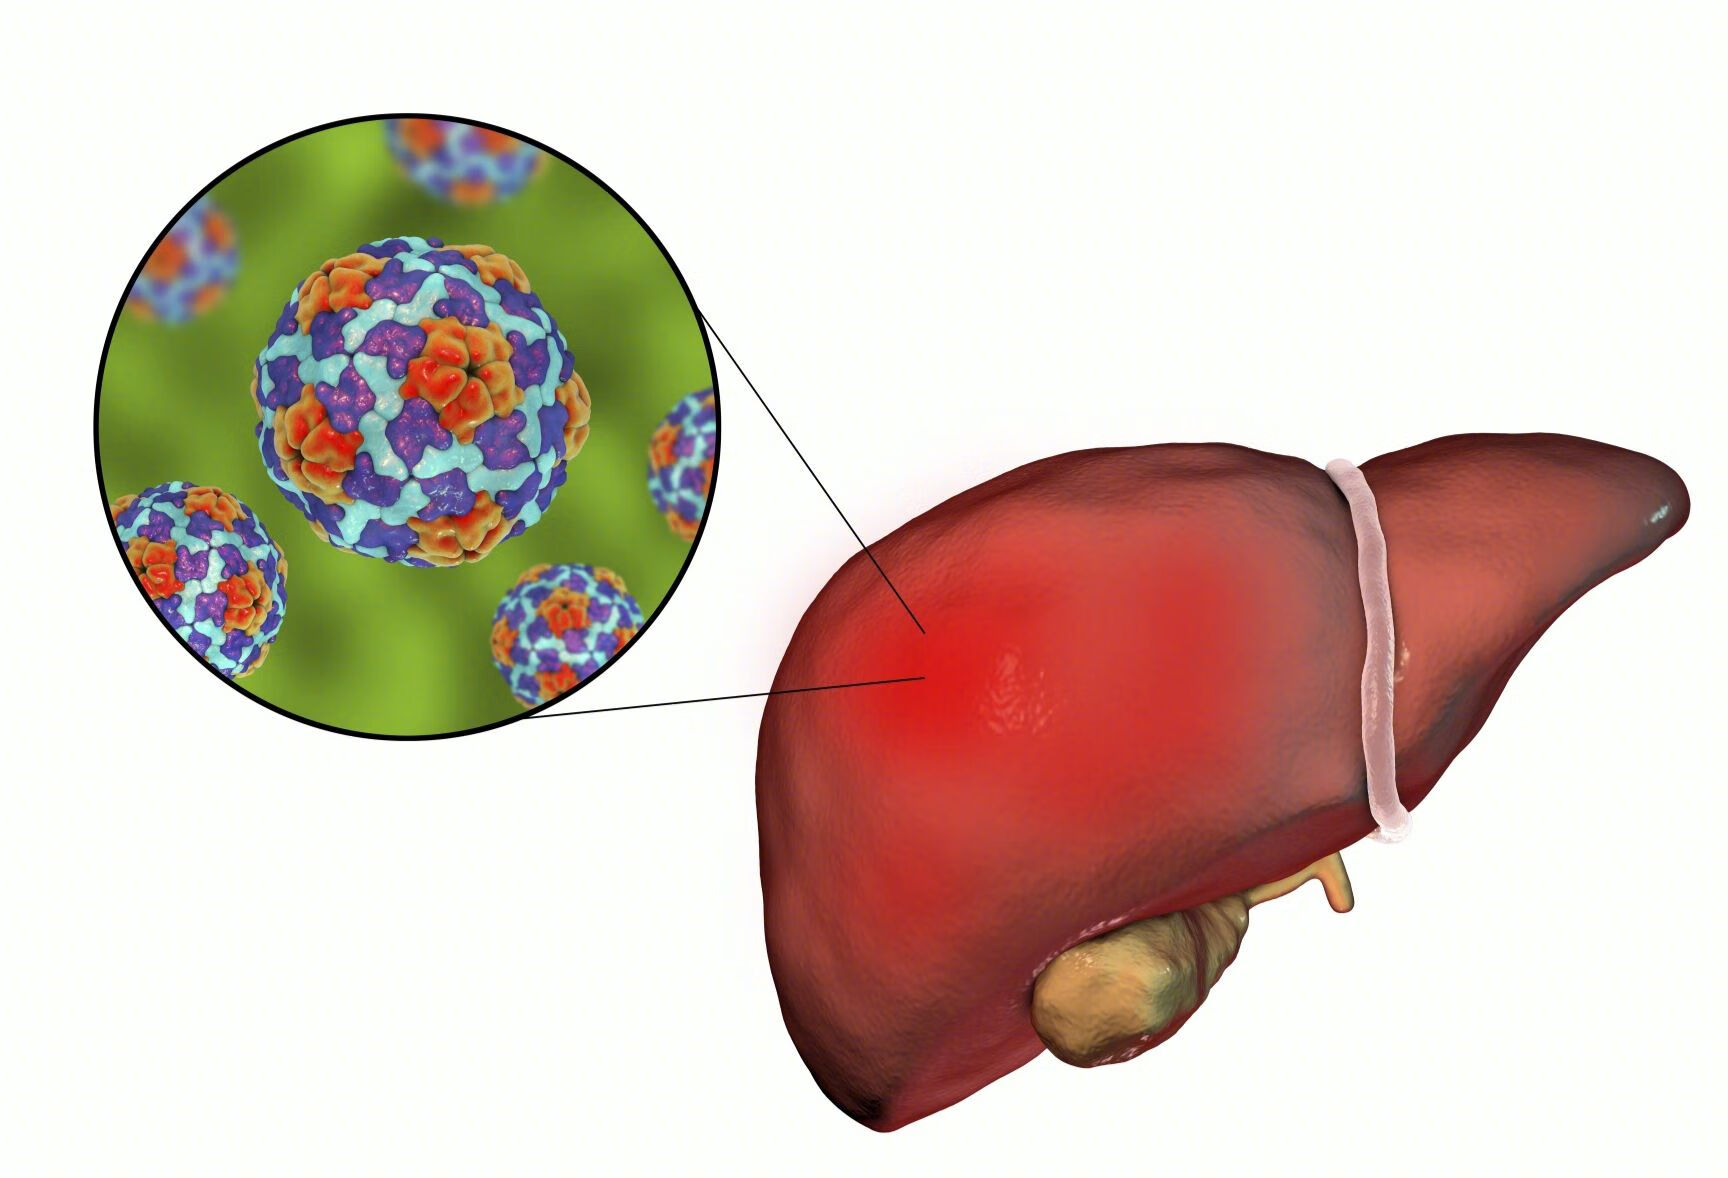

目前治疗小三阳的两种方法

就这个患者的情况而言,自己是乙肝小三阳,家族中有肝癌家族史,那么患者是需要密切监测,必要时候需要积极的抗病毒治疗。

目前我们的抗病毒治疗方案有两种

口服的核苷酸类似物以及肌注的干扰素。

口服药只能抑制病毒的复制,对于DNA能测到的患者来说,口服药可以抑制病毒的复制,从而阻断病情的进展,预防肝硬化和肝癌的发生。

这个患者没有抗病毒治疗,但是检测DNA小于500,理论上可以不用抗病毒治疗。注意定期复查就行。当然对于这种患者建议检查高敏DNA,可以测到10个以上的病毒。如果能测到病毒,结合家族史,就要在39岁以前开始抗病毒治疗。

如果还是没有测到病毒,表面抗原小于1500的话,可以考虑应用干扰素,有机会清除表面抗原。

干扰素还有一个好处就是:可以抗病毒,抗纤维化,抗肿瘤。